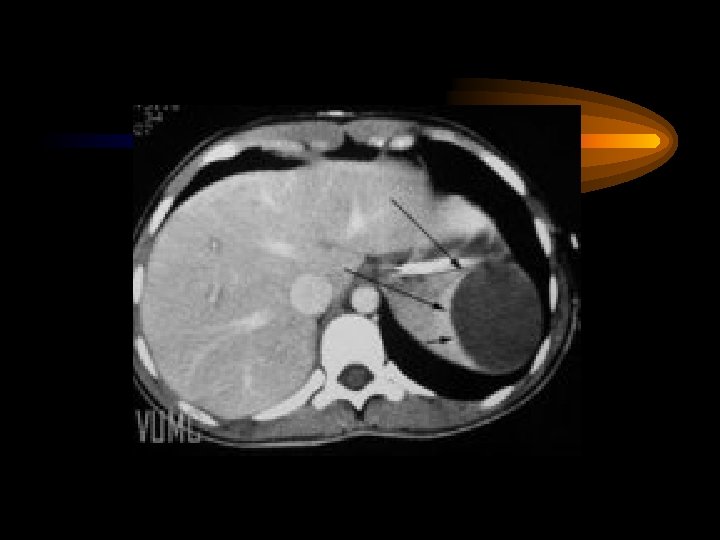

Pankreas Akut pankreatitis Karın ağrısı, bulantı-kusma, şok Nedenler Safra kesesi-yolları taşları Alkol Virüsler Hiperlipidemi, İatrojenik Tanı Serum amilazı yükselir Abd. CT ve US komplikasyonlar pseudokist, flegmon abse